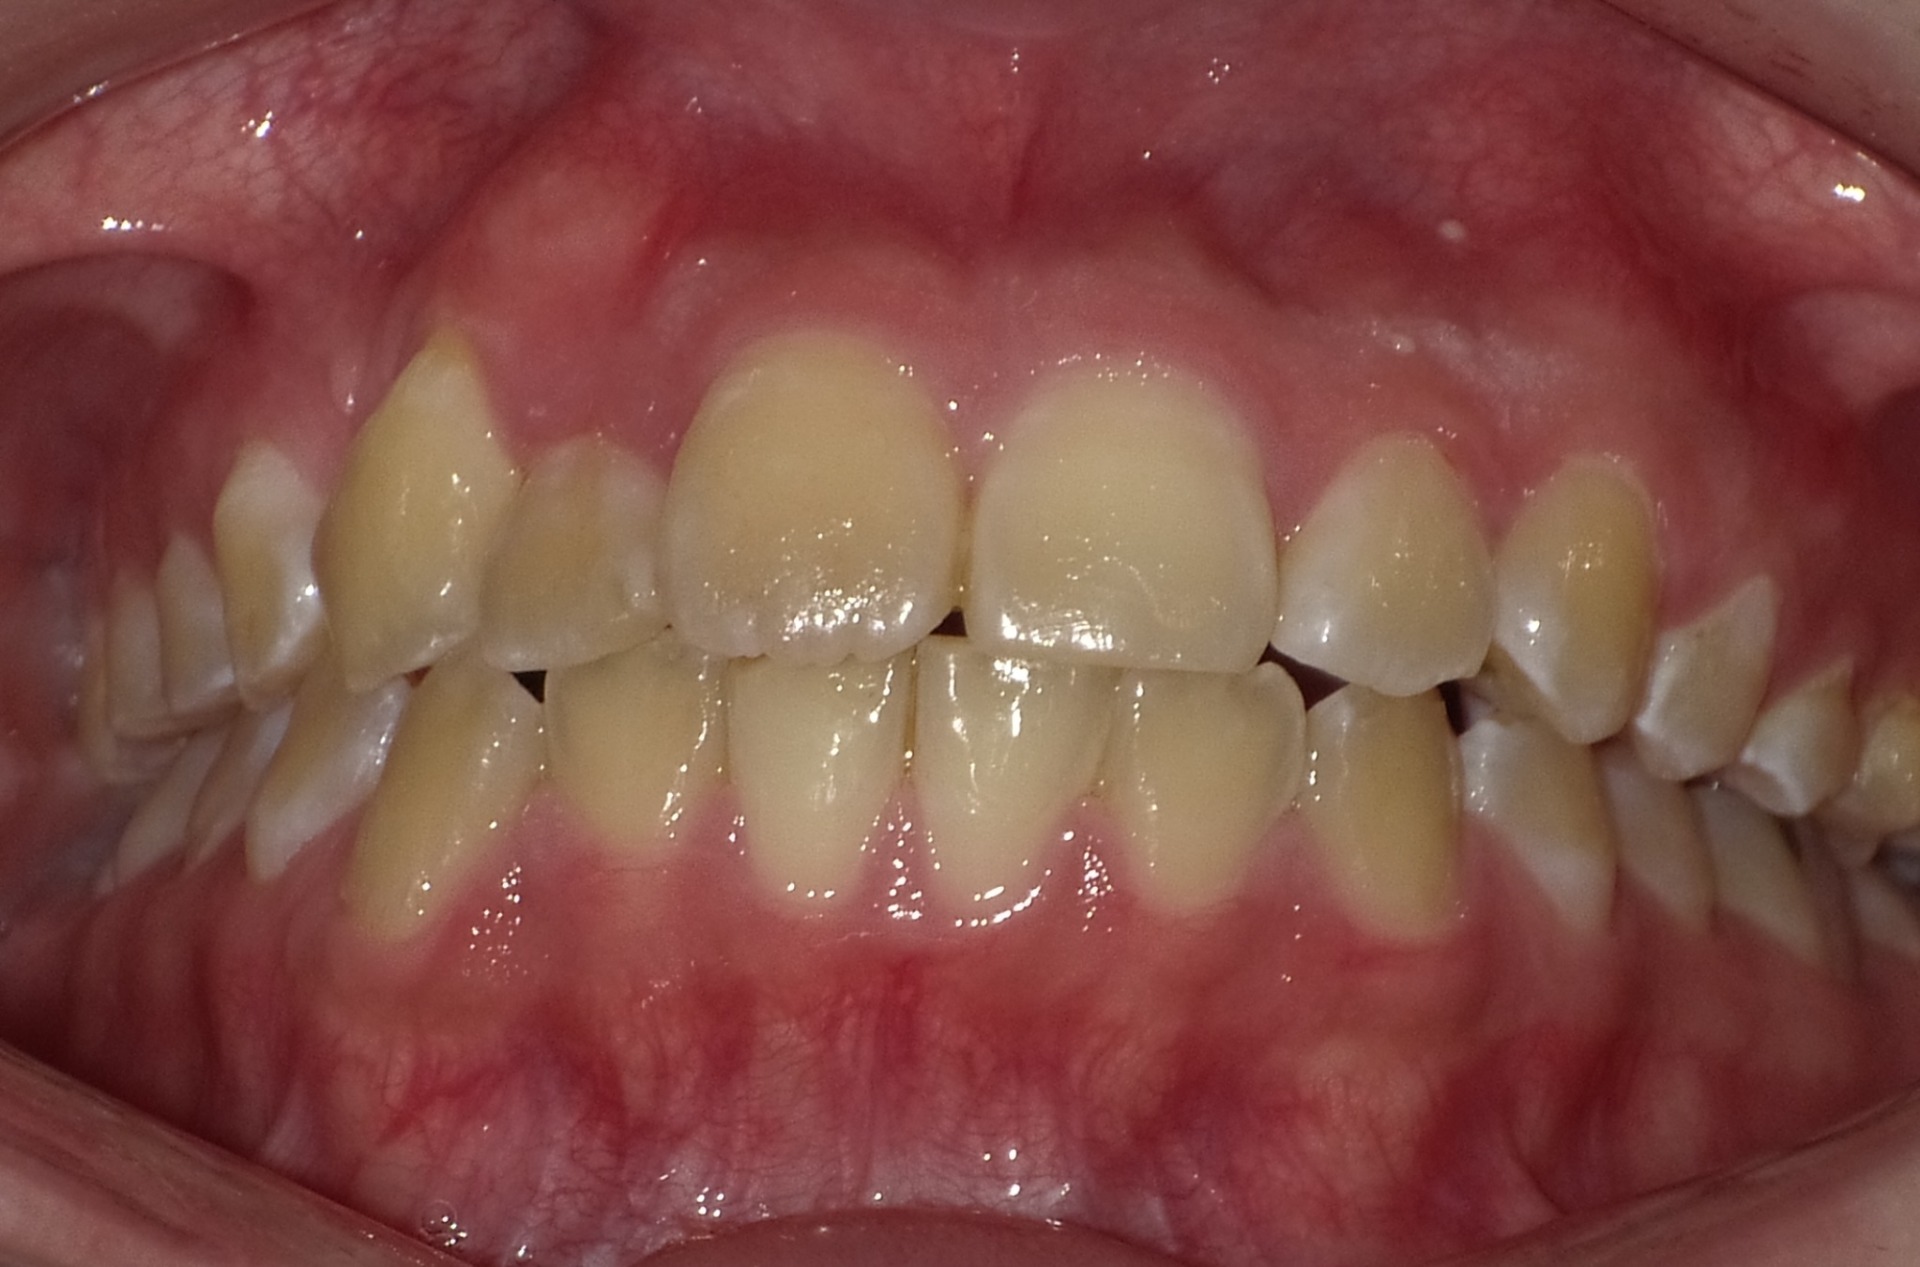

矯正後

| 症状 | 左上2番3番逆転症例 |